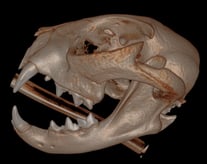

A cat presented with a temporomandibular joint (TMJ) luxation after a fall from a shelf. Initial attempts to reposition the TMJ at an emergency clinic were followed by a referral to ensure no fractures. The treatment involved the 'button' technique for TMJ stabilization, which was successful after three weeks of esophageal tube feeding. Post-treatment, the cat returned to normal function, although slight TMJ mobility and subluxation were noted. Imaging confirmed no fractures, and Ethilon with 3 buttons was used for stabilization, to be removed in 7-14 days. Follow-up imaging, specifically Cone Beam Computed Tomography (CBCT), was recommended one year later to monitor dental development.